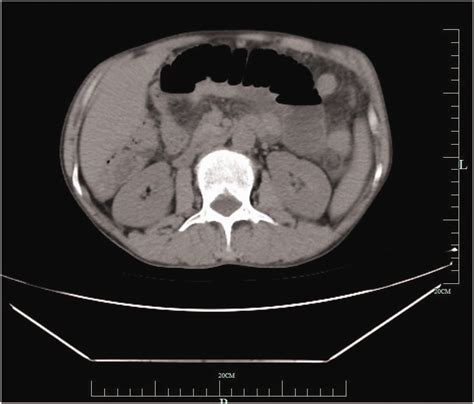

Because the Retroperitoneal Lymph Nodes are located deep within the torso, physicians rely on advanced diagnostic imaging to assess their size, shape, and health. When nodes become enlarged—a condition known as lymphadenopathy—it may indicate an infection, inflammation, or the presence of malignant cells. Determining the underlying cause of this enlargement is critical for developing an effective treatment plan.

• Computed Tomography (CT) Scans: The gold standard for visualizing these nodes. They provide detailed cross-sectional images of the abdominal cavity.